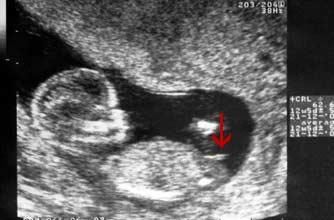

12週頸部透明帶猜性別之我猜不出來 媽咪拜mamibuy

懷孕 12週透明頸帶超音波 看板babymother Ptt網頁版

想請問有經驗的媽咪們 12週超音波寶寶性別 有圖 Babyhome親子討論區

12週超音波性別分辨 Babyhome親子討論區

12週做頸部透明帶 性別猜測 媽咪愛 育兒問答